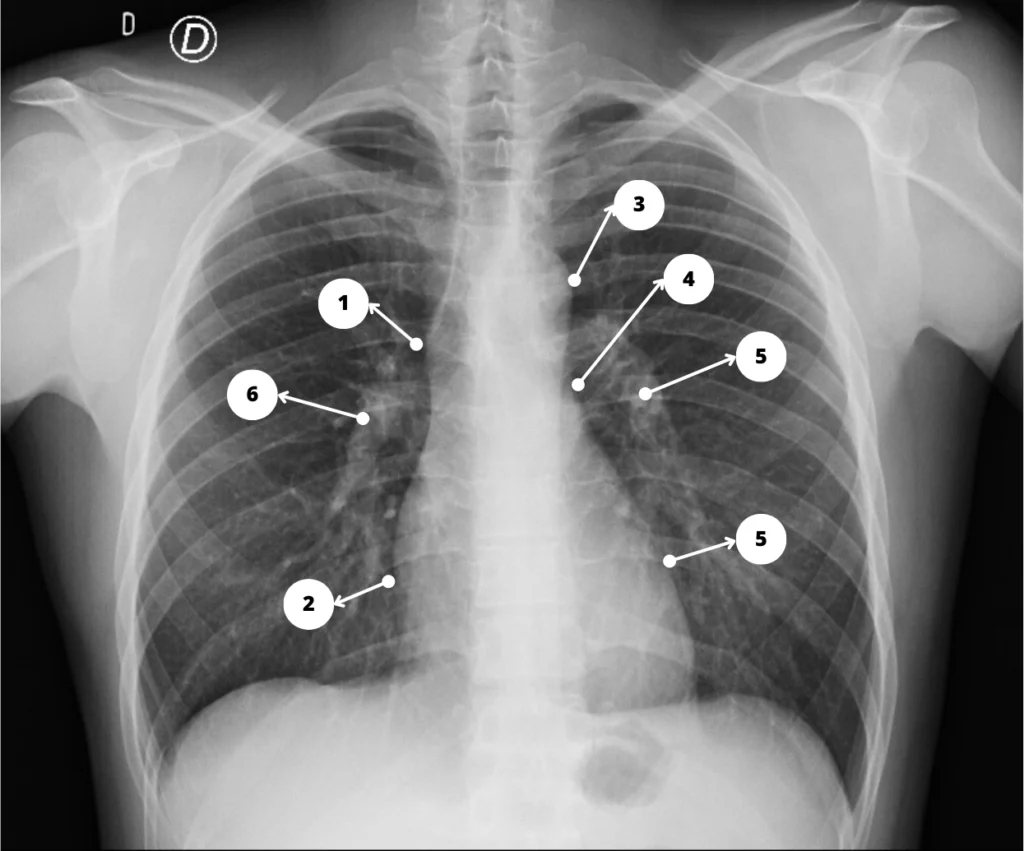

Mediastino en la Rx de tórax PA – 1. Vena cava superior; 2. Aurícula derecha; 3. Botón aórtico; 4. Arteria Pulmonar; 5. Ventrículo izquierdo; 6. Hilio derecho; 7. Hilio izquierdo.

La radiografía de tórax muestra contornos cardiomediastínicos normales. No se identifica masa pulmonar ni pleural.

Una comprensión profunda de las estructuras que normalmente contribuyen al contorno cardiomediastínico es esencial para poder interpretar las radiografías de tórax y localizar anomalías.